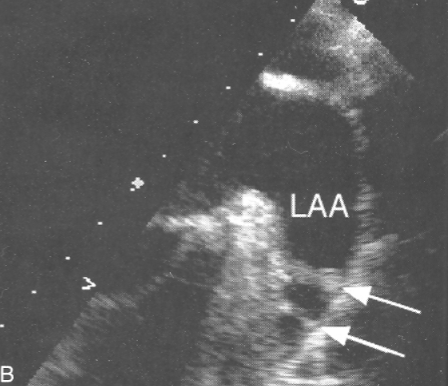

Ridge of Marshall AKA:

Coumadin Ridge

Warfarin Ridge

Ridge of Marshall

tissue separating LAA and LUPV

may be confused w/ clot